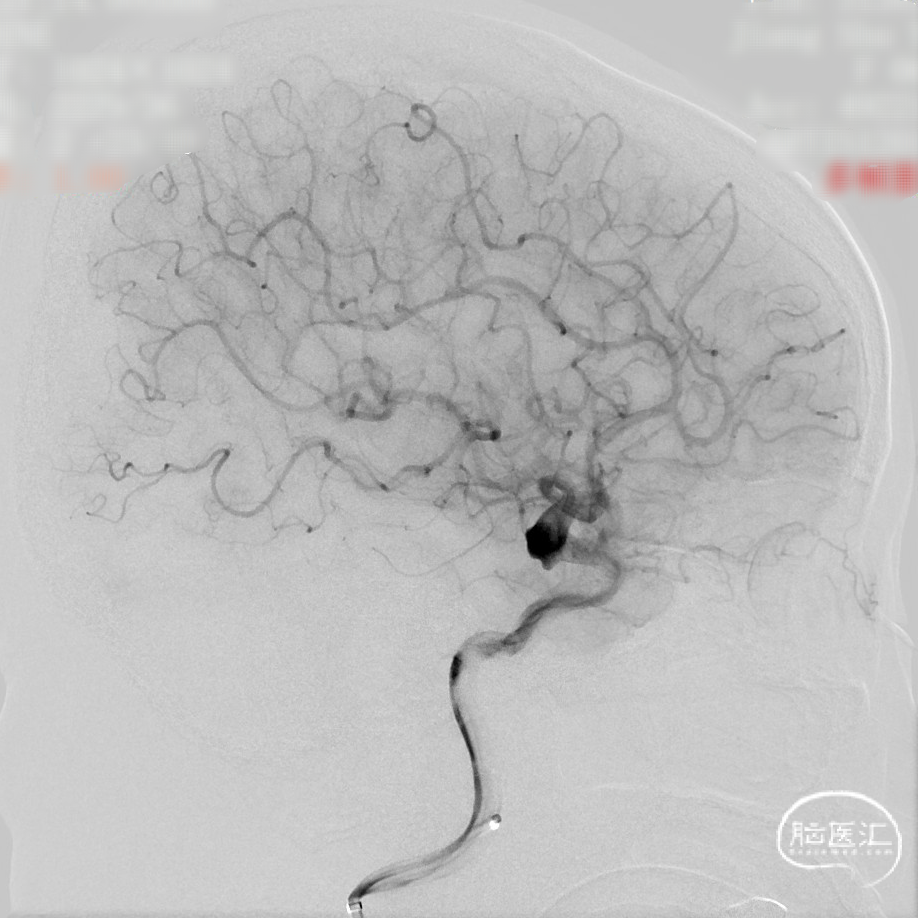

CTA:右侧颈内动脉C7段动脉瘤。

老年女性患者,检查发现右侧颈内动脉C7段大动脉瘤,动脉瘤直径大于10mm,形态不规则,宽颈,手术指征明确,既往高血压、肿瘤病史,首选微创介入手术,术中造影证实动脉瘤直径大于10mm,绝对宽颈,形态不规则,局部仔瘤改变,右侧脉络膜前动脉从瘤体发出;微创介入血流导向装置是较优选择。

DSA造影:

正侧位造影:支架放置后可见动脉瘤内造影剂明显滞留。